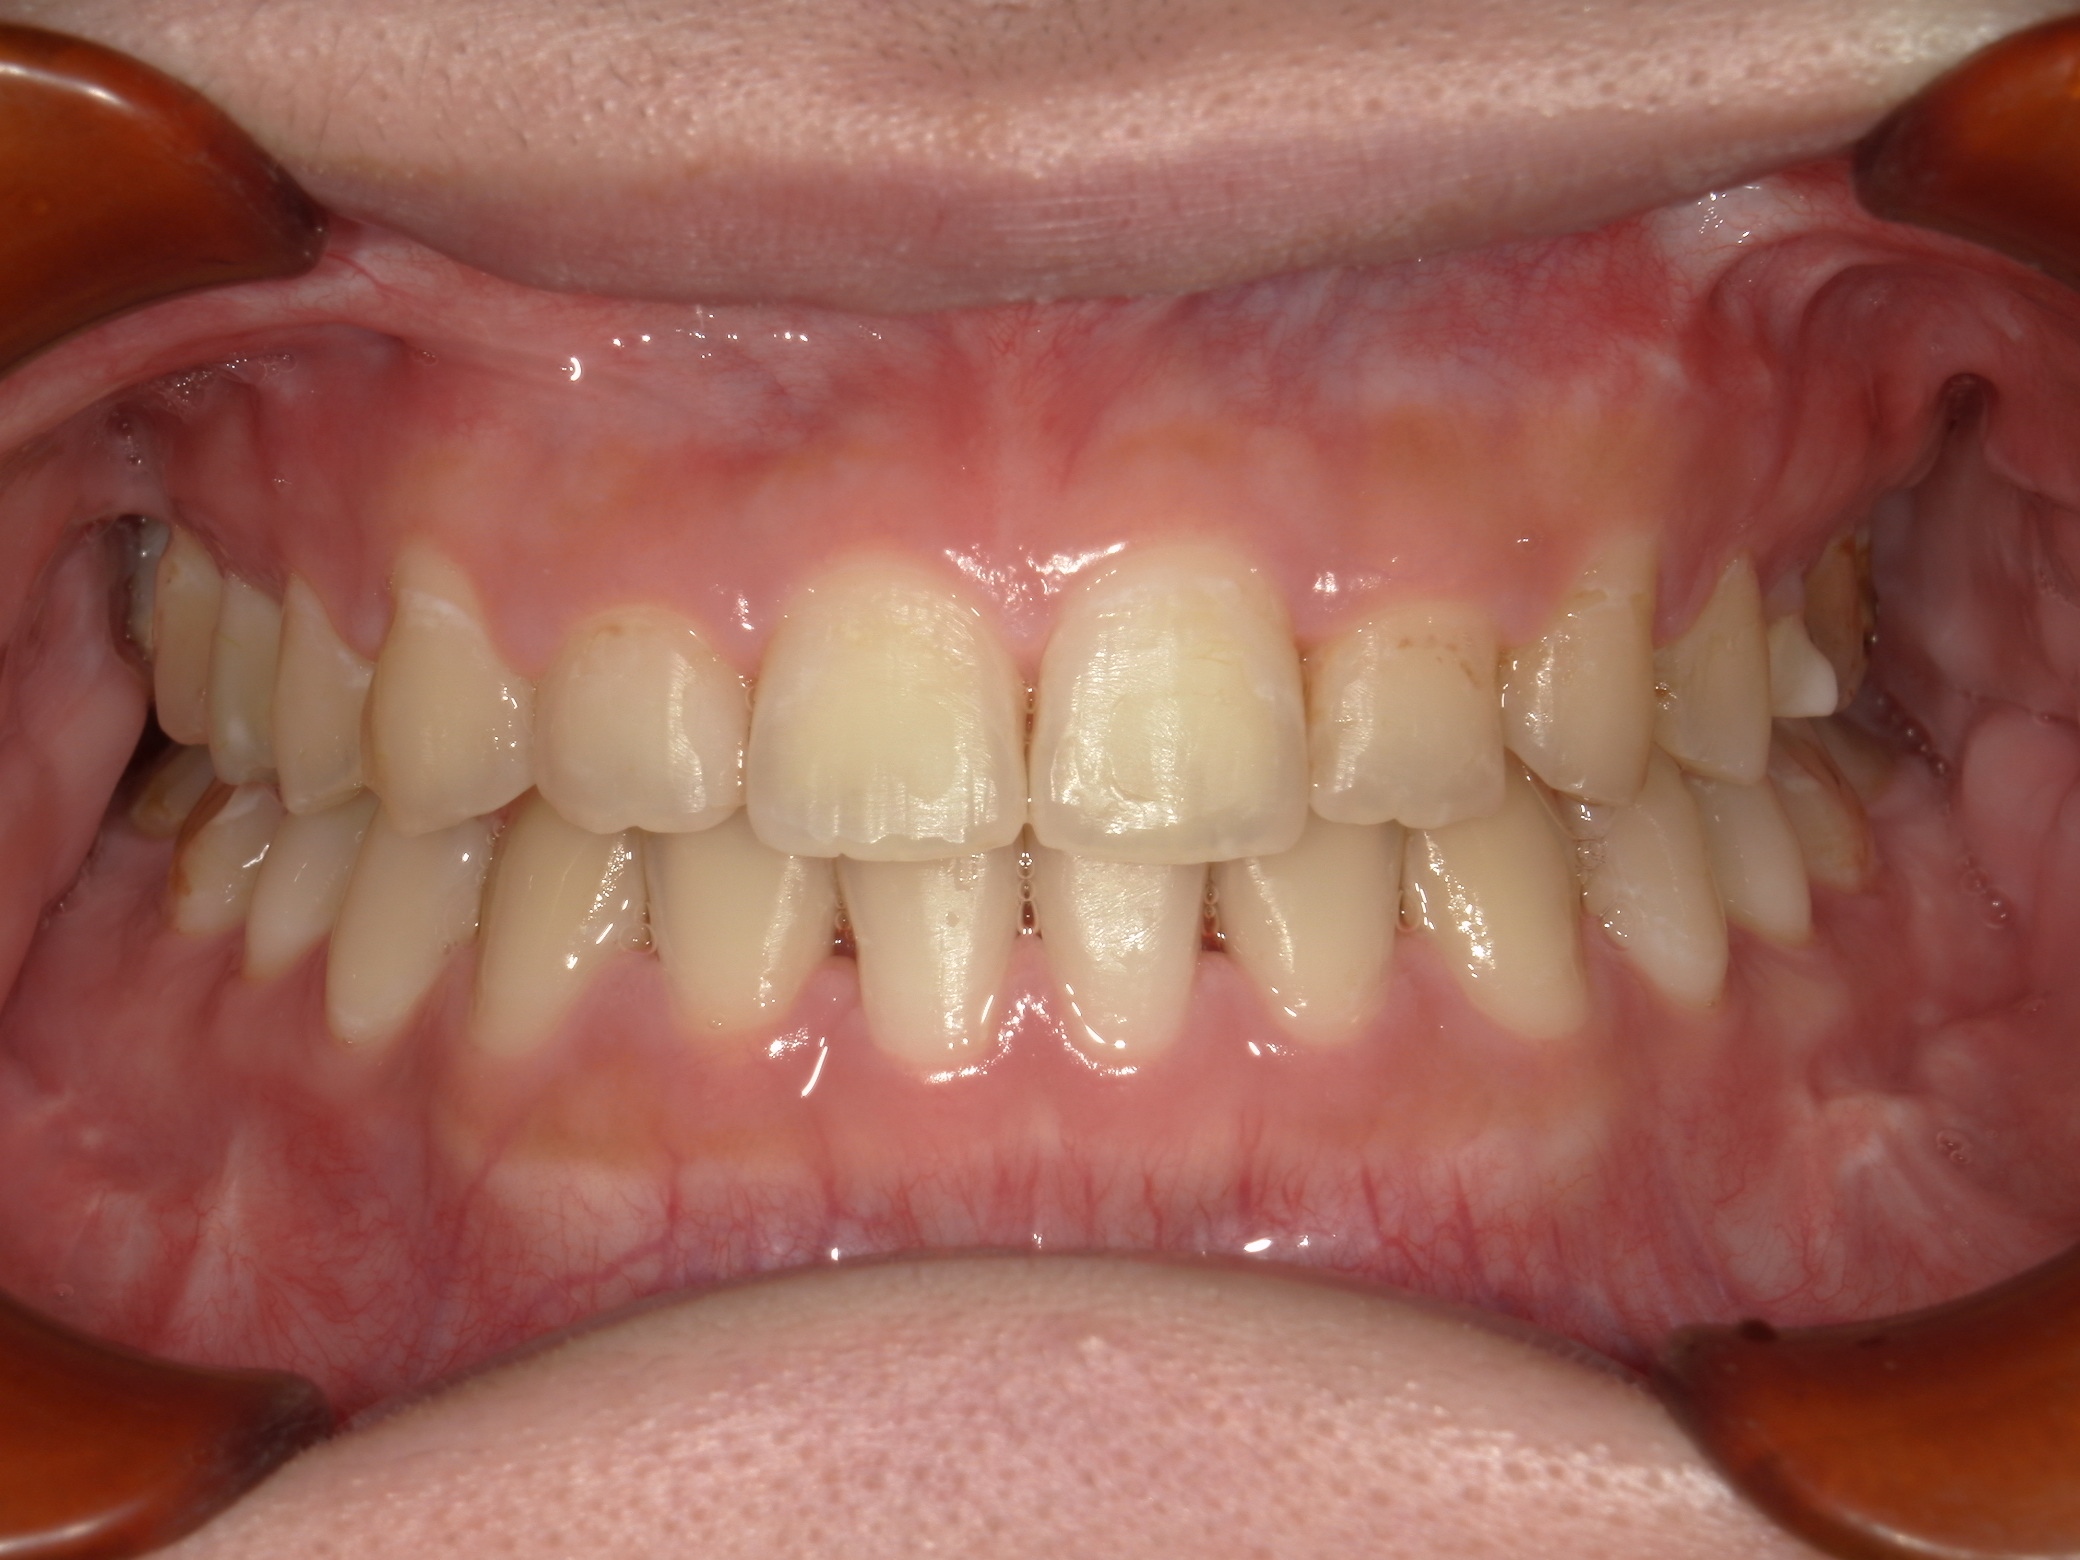

口内正面

治療前

上下の歯列のがたつきは軽度でしたが、下あごの骨が前方に位置しており、上下の前歯が突き合わせの咬み合わせになっていました。

セファロ写真の分析の結果を踏まえ、上下顎の外科的矯正治療を行うこととしました。

上下の歯を並べた後、上下のあごの骨を切って動かす手術を行い、骨格から改善を行いました。

結果、治療後の写真の通り正中は一致し、犬歯・臼歯ともに正しいポジションにて、美しい見た目と適切なかみ合わせを獲得できました。